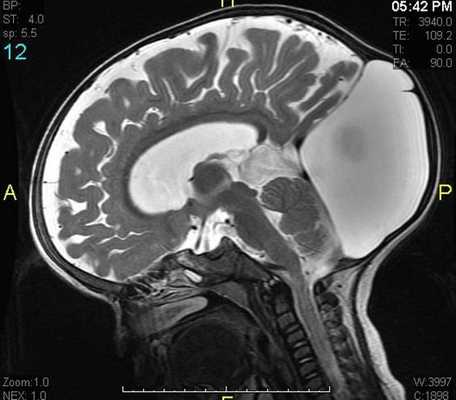

Пинеальная киста расположена в проекции шишковидной железы. Встречается с частотой 4-11%. Размеры обычно не превышают 1 см, но изредка встречаются больших размеров. В таких случаях она вызывает окклюзионную гидроцефалию. При головного мозга она имеет все признаки кисты с примесью белка в жидкости, то есть немного светлая на Т1-взвешенных. Изредка встречается геморрагическое содержимое. Киста может контрастироваться по периферии.

МРТ головного мозга. Сагиттальная Т1-взвешенная МРТ. Пинеальная киста.